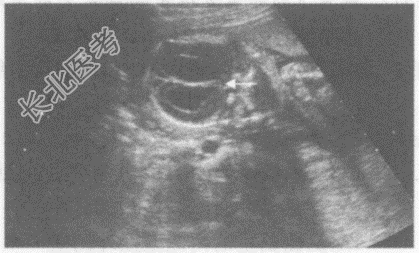

- 单项选择题临床资料:女性, 32岁,孕21周。

超声综合描述: 颅骨未见明显扩大,双顶径与孕周相符, 侧脑室扩大,内见无回声。

其超声提示:  A、露脑畸形

B、脑积水

C、脊膜膨出

D、无脑儿

E、脑膜膨出